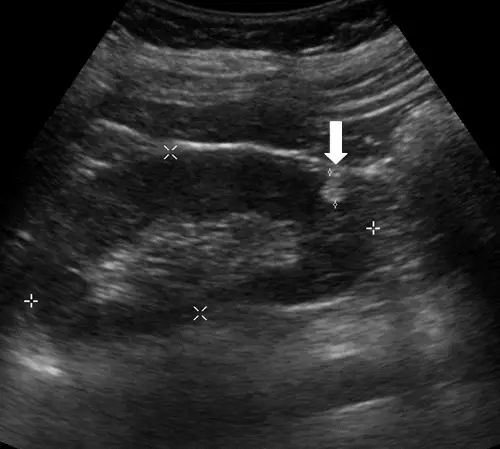

下圖為超音波影像,箭號所指處最可能為下列何者? 圖片

本題超音波影像為腎臟掃描,白色箭號指向腎臟實質內一個邊界清楚、明顯高回音(markedly hyperechoic)的局部病灶。

• 回音強度:病灶回音強度明顯高於周圍腎實質,其亮度接近腎竇脂肪(renal sinus fat)的回音強度,呈現極高回音

• 聲影(posterior acoustic shadow):病灶後方無明顯聲影,排除結石的可能性(結石後方應有清晰強聲影)

• 內部回音:病灶內部呈均勻高回音,無囊性暗區,排除水囊(anechoic with posterior enhancement)

• 邊界:病灶邊界尚清楚,無低回音暈環(hypoechoic rim,此為 RCC 的特徵之一)

• 形態:病灶相對小型,與腎實質邊界清楚

綜合以上特徵——極高回音 + 無聲影 + 無囊性成分 + 無低回音暈環——最符合脂肪豐富型血管平滑肌脂肪瘤(fat-rich AML)